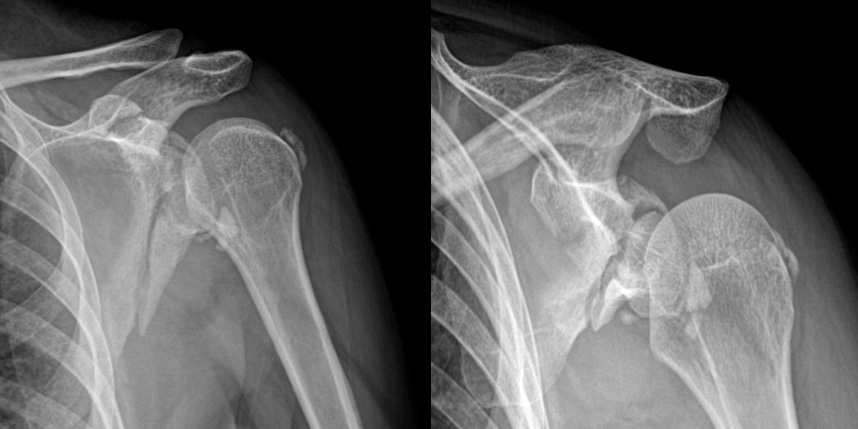

상완골 골절